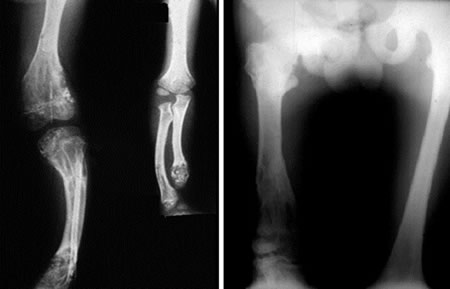

Enchondromatose Ollier : Asymétrie des lésions

unilatéralité dans 50% des cas responsable d'inégalités des membres avec incurvation.

Unilatéralité dans 50% des cas.

Inégalités des membres

inférieurs.

Boiterie avec incurvation (genou, cheville).

Inégalités des membres.

Evolution de lésions de la hanche Enchondromatose (Ollier)